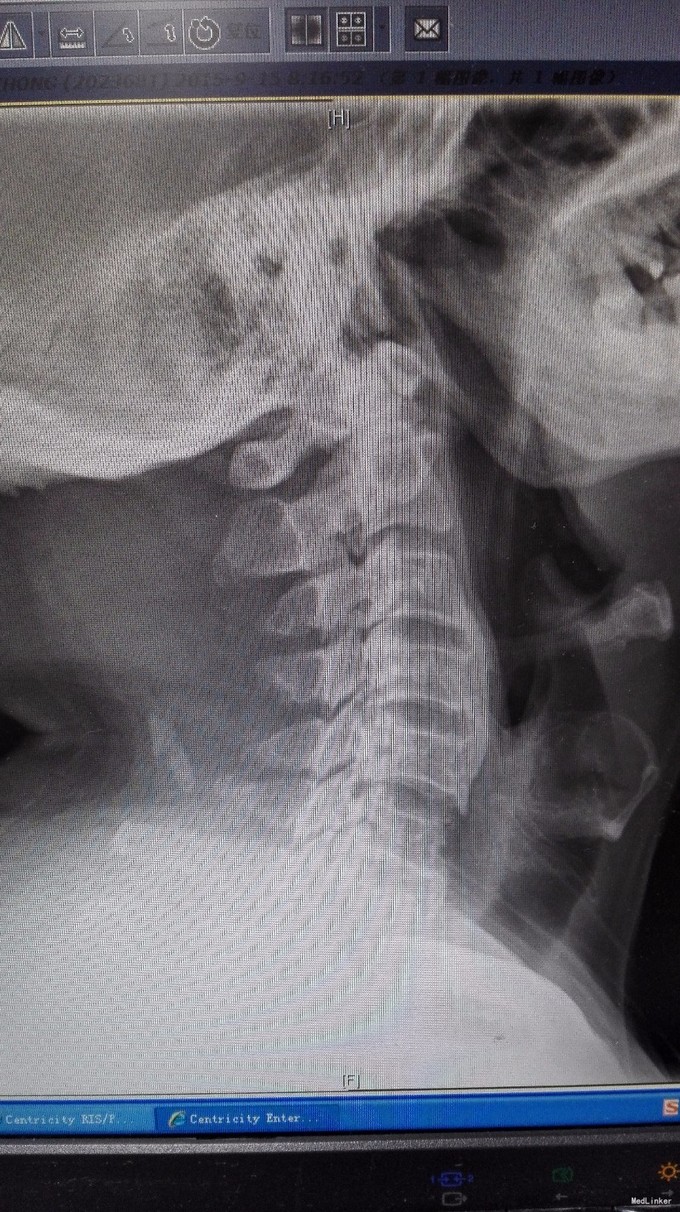

查体:双手麻木感,肱三头肌肌腱反射活跃,左侧髂腰肌4级,臂丛牵拉实验阴性,椎间孔挤压实验阴性。 辅查:CT:C2-7椎间盘突出,继发性椎管狭窄,OPLL,OFL。

诊断:混合型颈椎病(脊髓型+神经根型) 治疗:颈后路3-7单开门椎管扩大成型术(锚定法)